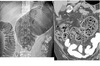

Menetriers disease

SPARES the antrum

Hyperplastic gastropathy/ protein-losing gastropathy

Grossly thickened, lobulated folds in gastric fundus and body with poor barium coating. low albumin

CT - Massive thickening of mucosa and submucosa, giant, mass-like, tortuous folds resemble cerebral convolutions

DDx

Gastritis - thickened lobulated folds favour antrum

ZES - Multiple ulcers, pancreatic tumor (gastrinoma)